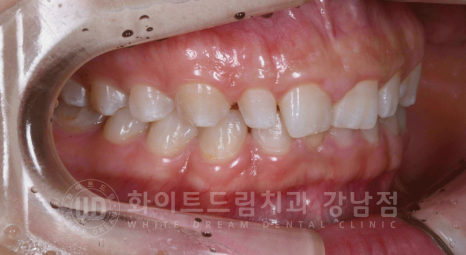

환자분은 치아의 길이가 굉장히 짧습니다.

부착치은(잇몸)이 치아를 덮고 자라 치아 길이가 짧아져 보이는 것인데요.

치아를 덮고 있는 잇몸을 살짝 레이저로 다듬어 늘씬한 치아 모양으로 개선을 해주는 방법입니다.

잇몸의 높낮이를 맞추면서 환자분처럼 치아의 길이가 짧아 답답한 인상을 시원하게 개선할 수 있습니다.

환자분은 잇몸도 굉장히 건장하고 부착치은이 풍성한 상태여서 잇몸성형술로 이 부분을

살짝 제거하여 길고 시원한 잇몸라인을 만들고, 라미네이트 부착을 위해 최소한의 치아 삭제를 진행했습니다.

유튜브에서나 보던 심각할 정도의 치아 삭제는 라미네이트 진료 시 진행하지 않으며,

치아 겉면을 살짝 다듬는 정도의 최소한의 치아 삭제만 진행한답니다.